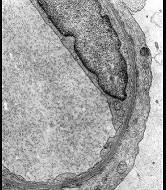

问题 肾病理光镜及免疫荧光正常,观察电镜下改变,其病理诊断 ( )

选项 A.正常肾小球 B.膜性肾病 C.膜增生性肾小球肾炎 D.系膜增生性肾小球肾炎 E.微小病变

答案 E